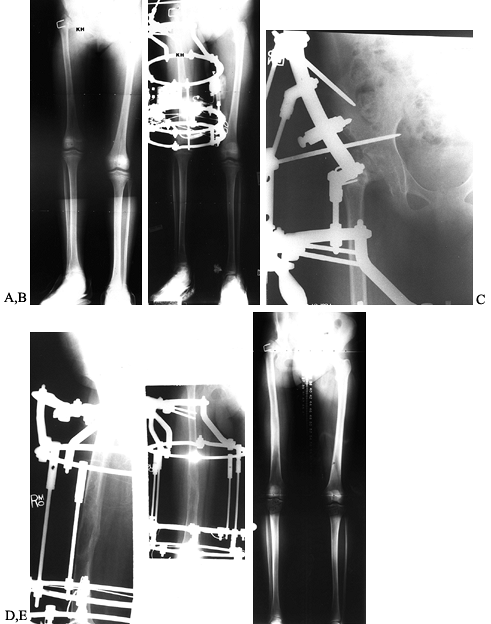

Figure 171.24. A and B:

Standing and lateral teleoroentgenograms of a patient with Ollier’s disease and a 13 cm limb-length inequality with bifocal tibial deformity. C and D: The Ilizarov external fixator with bifocal application was used for gradual correction of the proximal and distal deformities as well as 8 cm of lengthening. E: Radiographs at the conclusion of tibial consolidation. |